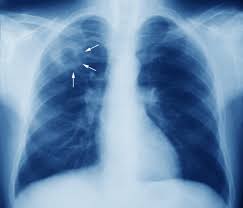

يمكن تشخيص مرض السل الرئوي / الدرن من خلال عمل اشعة للرئة و كذلك عمل شريحه لعينه بلغم مصبوغة بطريقة الصبغ الصامد تجاه الاحماض Acid-fast staining او ما يعرف بطريقة زيل-نيلسين Ziehl-Neelsen method و يكون لون الخلايا احمر وردي (صبغة كاربول فوكسين)